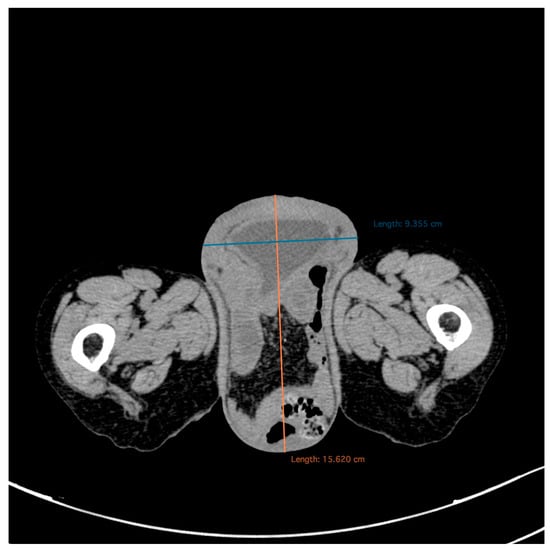

2. Case Report